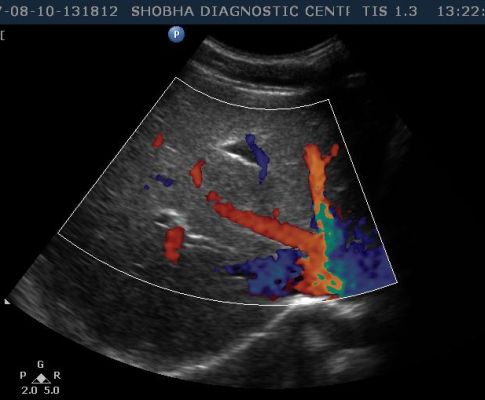

- Abdominal Doppler

- RENAL ARTERY

- AORTA

- IVC

In color Doppler the blood circulation is assessed. It is more often done in diabetic patients, in chronic smokers who are more prone to develop blockage in their arteries, in patients who suffer from varicose vein problem.

It is non invasive test which tells you about blood circulation to any particular part of the body like upper limb, lower limb, blood supply to any tumor or swelling involving the body.